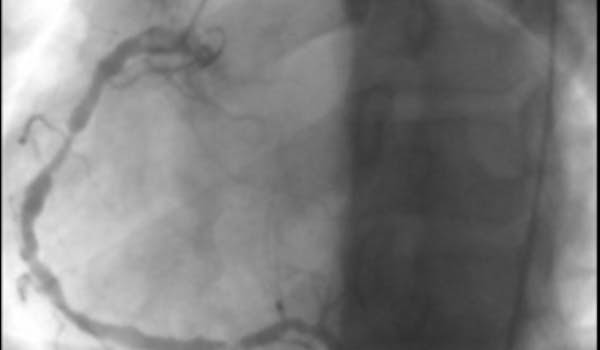

Il s'agit d'une vascularite des artères de gros et moyen calibre, d'étiologie inconnue, qui touche préférentiellement le nourrisson et l'enfant de moins de 5 ans, plus rarement l'adulte. Le syndrome de Kawasaki réalise un syndrome adéno-cutanéo-muqueux fébrile. Sa gravité est liée à l'atteinte cardiaque et au développement d'anévrismes coronaires qui peuvent être à l'origine de mort subite.